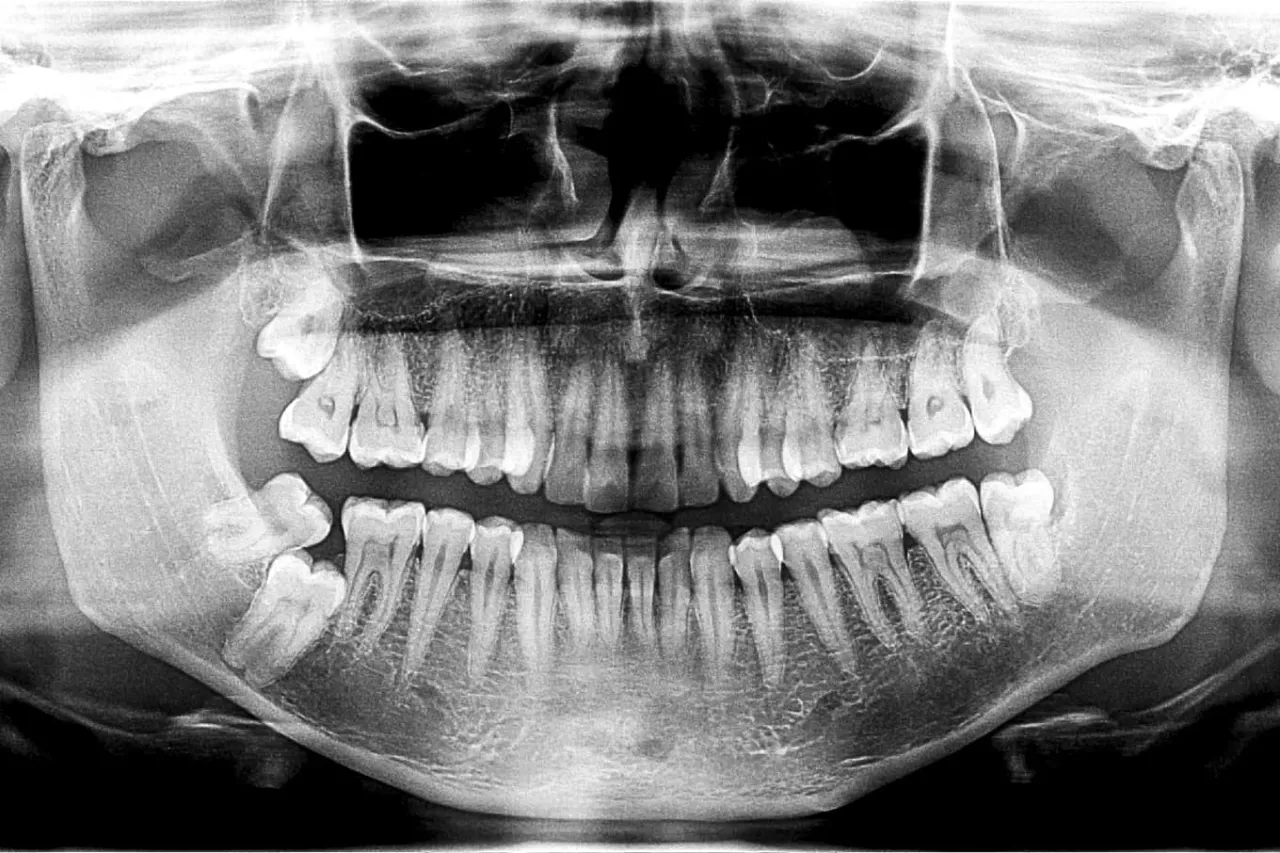

Kluczowy pierwszy krok: Diagnostyka, czyli jak dentysta oceni sytuację (RTG, CBCT)

Pierwszym i najważniejszym etapem jest dokładna diagnostyka. Nie da się ocenić stanu zęba i otaczających go tkanek wyłącznie na podstawie oględzin. Dlatego stomatolog z pewnością wykona zdjęcie rentgenowskie (RTG), które pozwoli mi ocenić stan kości wokół korzenia, wykryć ewentualne stany zapalne, torbiele czy pęknięcia. W bardziej skomplikowanych przypadkach może być konieczne wykonanie tomografii komputerowej wiązki stożkowej (CBCT), która dostarcza trójwymiarowego obrazu struktur kostnych.